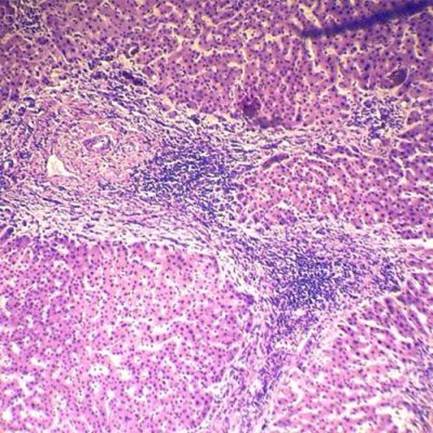

Хронический персистирующий гепатит (гистологический препарат)